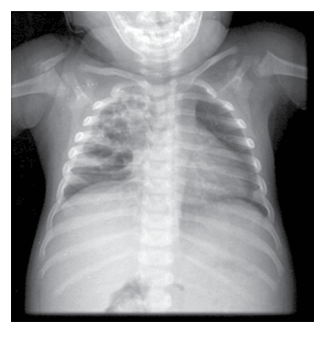

Paciente com 4 anos de idade, sexo masculino, dá entrada ao hospital com a mãe relatando que a criança iniciou quadro de febre (38,5°C) e tosse seca há 1 semana. Na internação apresenta a imagem radiológica apresentada na figura.